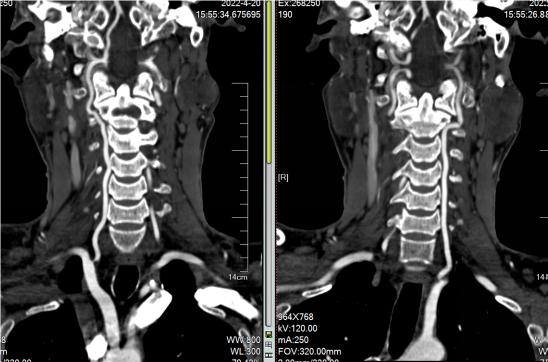

CTA:右侧颈内动脉、大脑中动脉未显影

病历夹什么径技·第152期|串联营病历夹:川陕大营_https://www.jmylbn.com_新闻资讯_第77张

病历夹什么径技·第152期|串联营病历夹:川陕大营_https://www.jmylbn.com_新闻资讯_第78张

病历夹什么径技·第152期|串联营病历夹:川陕大营_https://www.jmylbn.com_新闻资讯_第79张

<<滑动查看下一张图片>>

CTP:右侧大脑半球低灌注

病历夹什么径技·第152期|串联营病历夹:川陕大营_https://www.jmylbn.com_新闻资讯_第80张